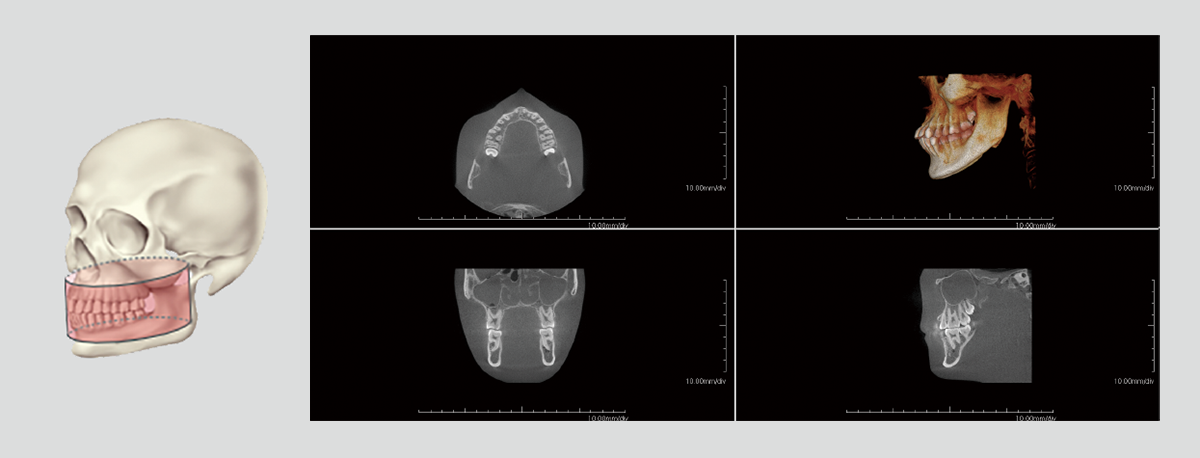

With dentists from various fields of expertise as advisors, we have carefully selected FOVs that are commonly used in clinical practice. In addition to the 3D analysis function for image detail sizes of 5x5cm, 10x10cm, 15x10cm and 15x16cm, the device features “True” and “Reconstructed” panoramic modes. With one of the largest FOVs on the market, the PreXion3D EXPLORER helps to develop the best therapy options, particularly in oral and maxillofacial surgery, airway analysis and orthodontics, as well as ear, nose and throat medicine. The use of a large 25.4x31.7cm FPD enables 15x16cm FOV scanning in one rotation.

The precise and high-resolution display of hard and soft tissue enables outstanding diagnostics and planning across all areas of modern dentistry and maxillofacial surgery. A large high-definition FPD allows all FOVs scanned in a single rotation without using stitching function.

With many 3D imaging systems on the market today, high-quality images are often accompanied by high radiation exposure. The PreXion3D EXPLORER offers balance of both aspects. The PreXion3D EXPLORER utilizes the industry’s smallest 0.3mm x-ray tube focal spot and voxel sizes from 0.07mm to 0.3mm for all FOV sizes. In addition, by adopting a high X-ray tube voltage of 110kV, pulsed X-ray irradiation, 16bit gray scale, and a newly developed large FPD, it simultaneously achieves high-definition image quality for a wide range of dental clinical practice and low radiation exposure for patient safety.